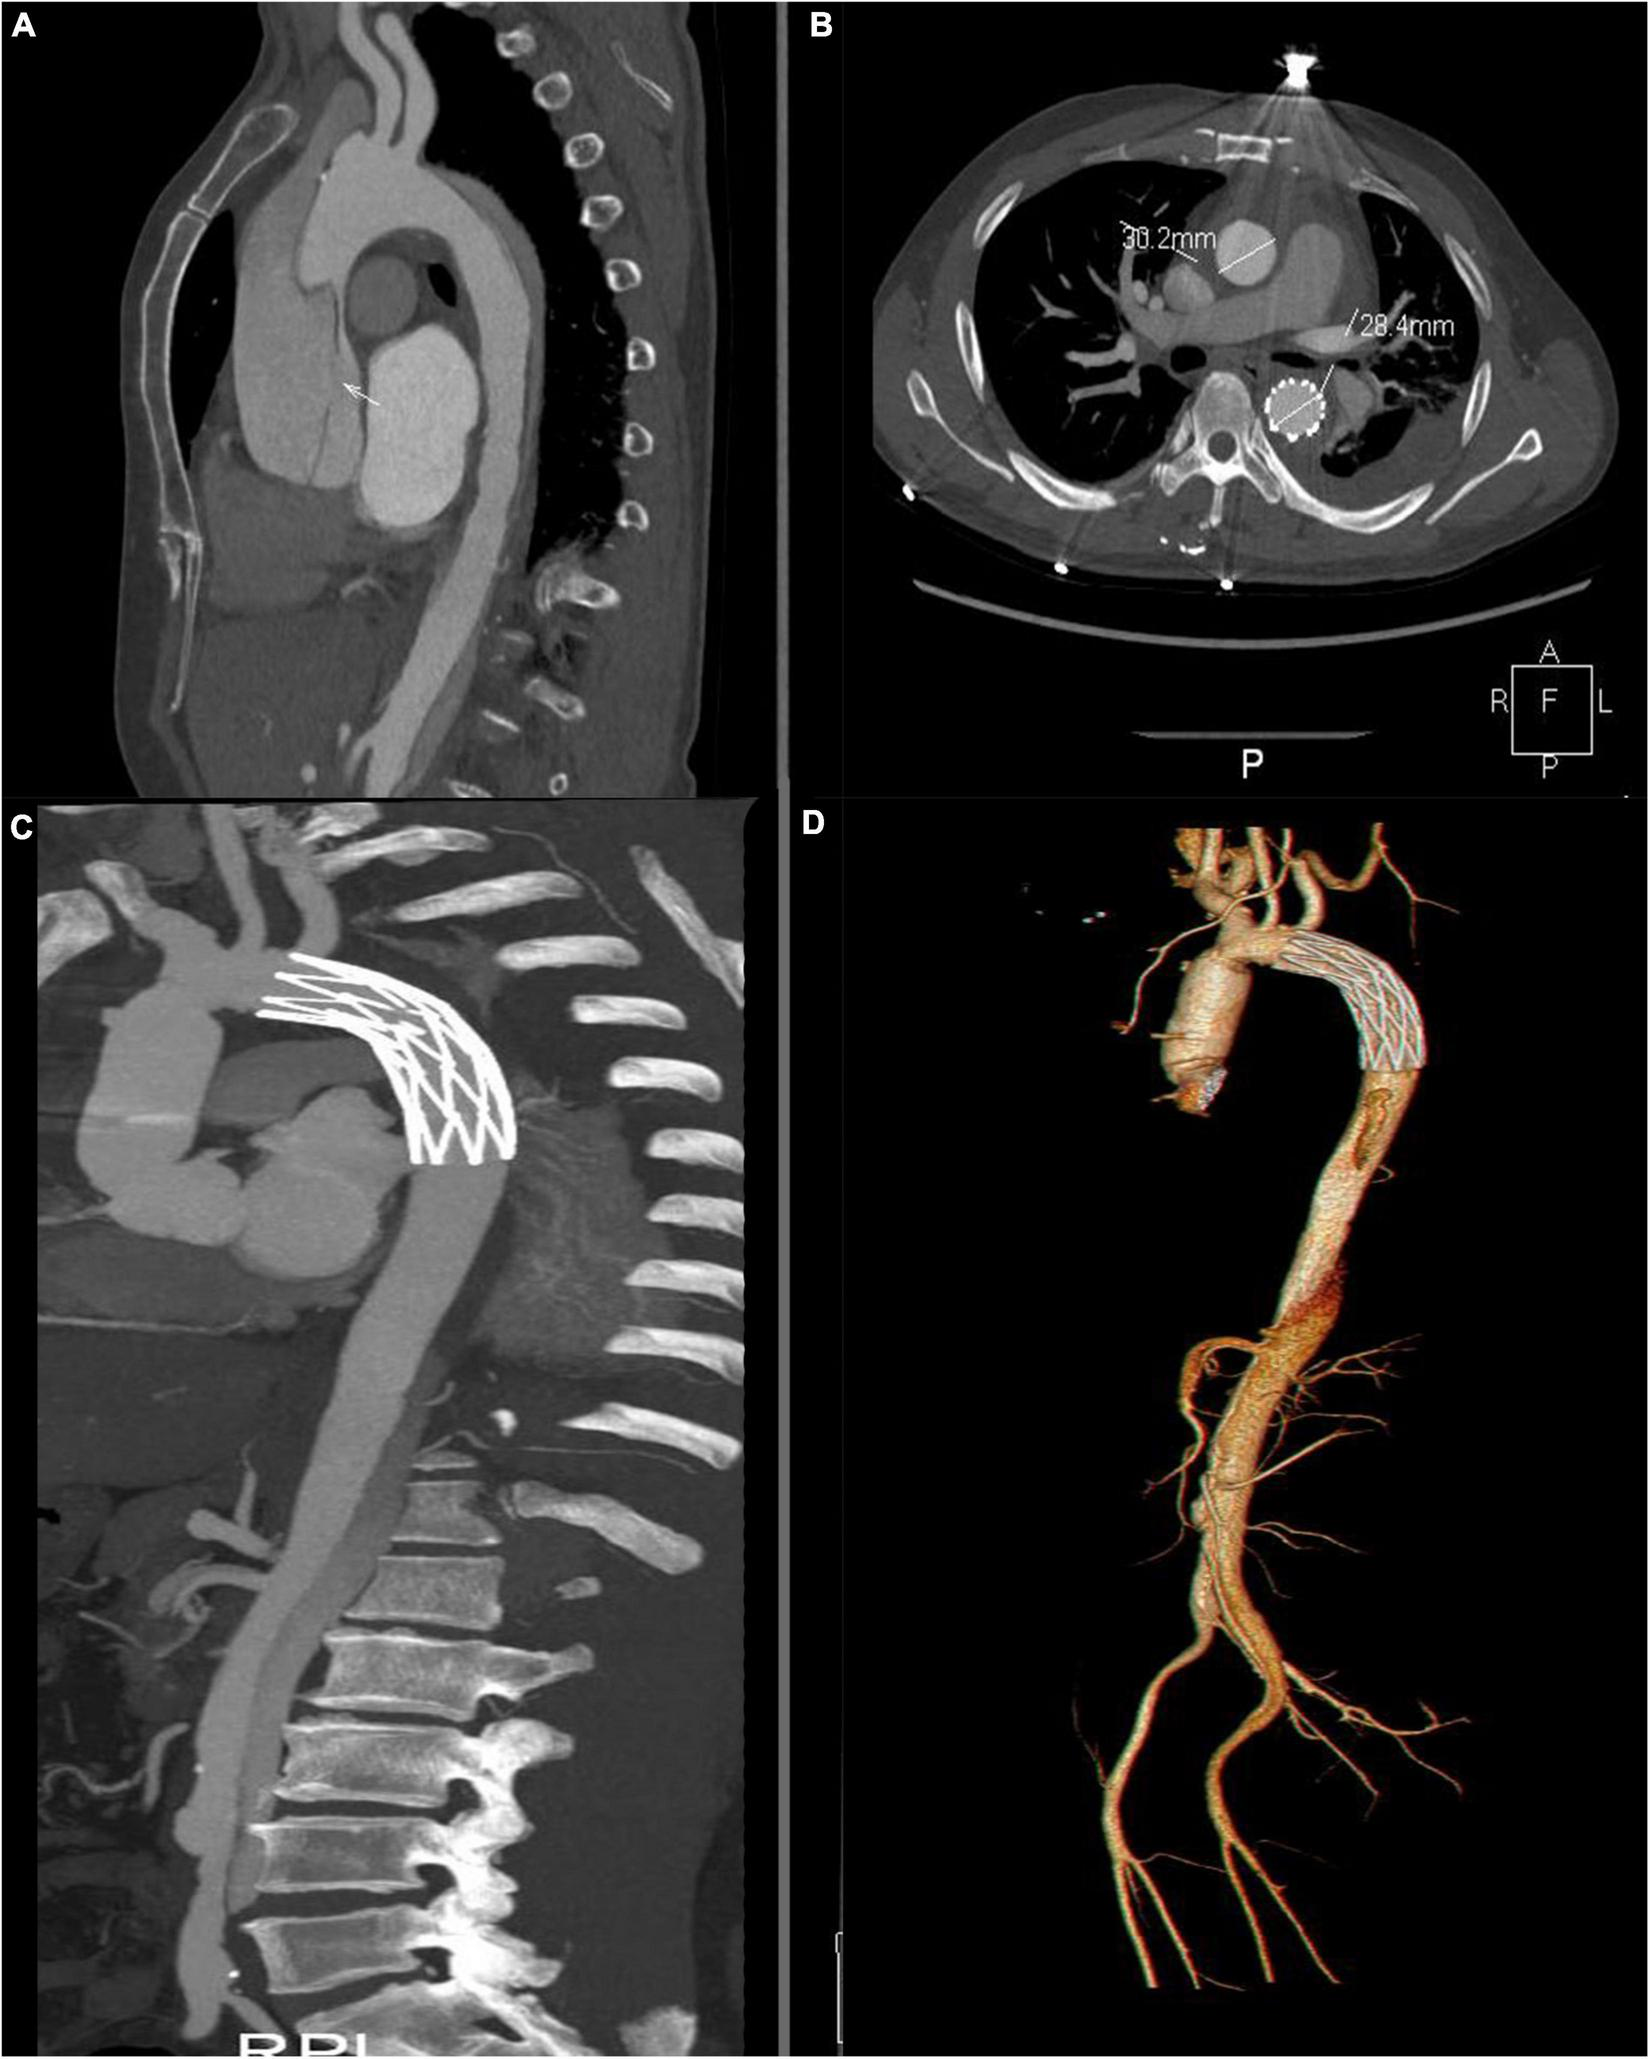

All of the patients underwent CTA examination in 6-32 months. False lumen closure rate of the descending aorta in ministernotomy group was found in 57 (83.8%) patients, while false lumen patency persisted in 3 (4.41%) patients and partial closure in 4 (5.88%). Complete aortic arch false lumen closure was achieved in 60 patients (88.2%) in ministernotomy group, which is significantly improved than 77.8% in full sternotomy group (P<0.05). Arch false lumen patency persisted in 3 (4.41%) patients and partial closure in 2 (2.94%) (Table 3 and Figure 4). Patients’ follow up CTA examination with false lumen patency persisted reported slightly enlargement comparing with preoperation. They were asymptomatic. Therefore, we continued to monitor these patients carefully (Table 4).

FIGURE 4

Computed tomography angiography assessment. (A) Intimal tear in the ascending aortic before the operation. The white arrow indicates the intimal tear. (B) Postoperative examination at 12 month. Thrombosis of the thoracic false lumen in descending aortic. (C,D) Postoperative volume-rendered image.